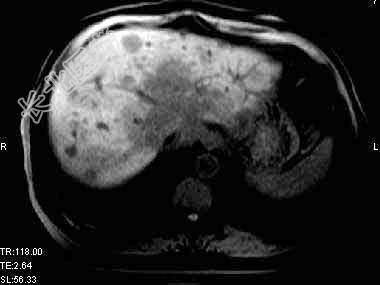

- 单项选择题根据所提供的图像,最可能的诊断是 ( )

A、肝转移癌

B、肝细胞癌

C、肝胆管细胞癌

D、肝血管瘤

E、以上都不是